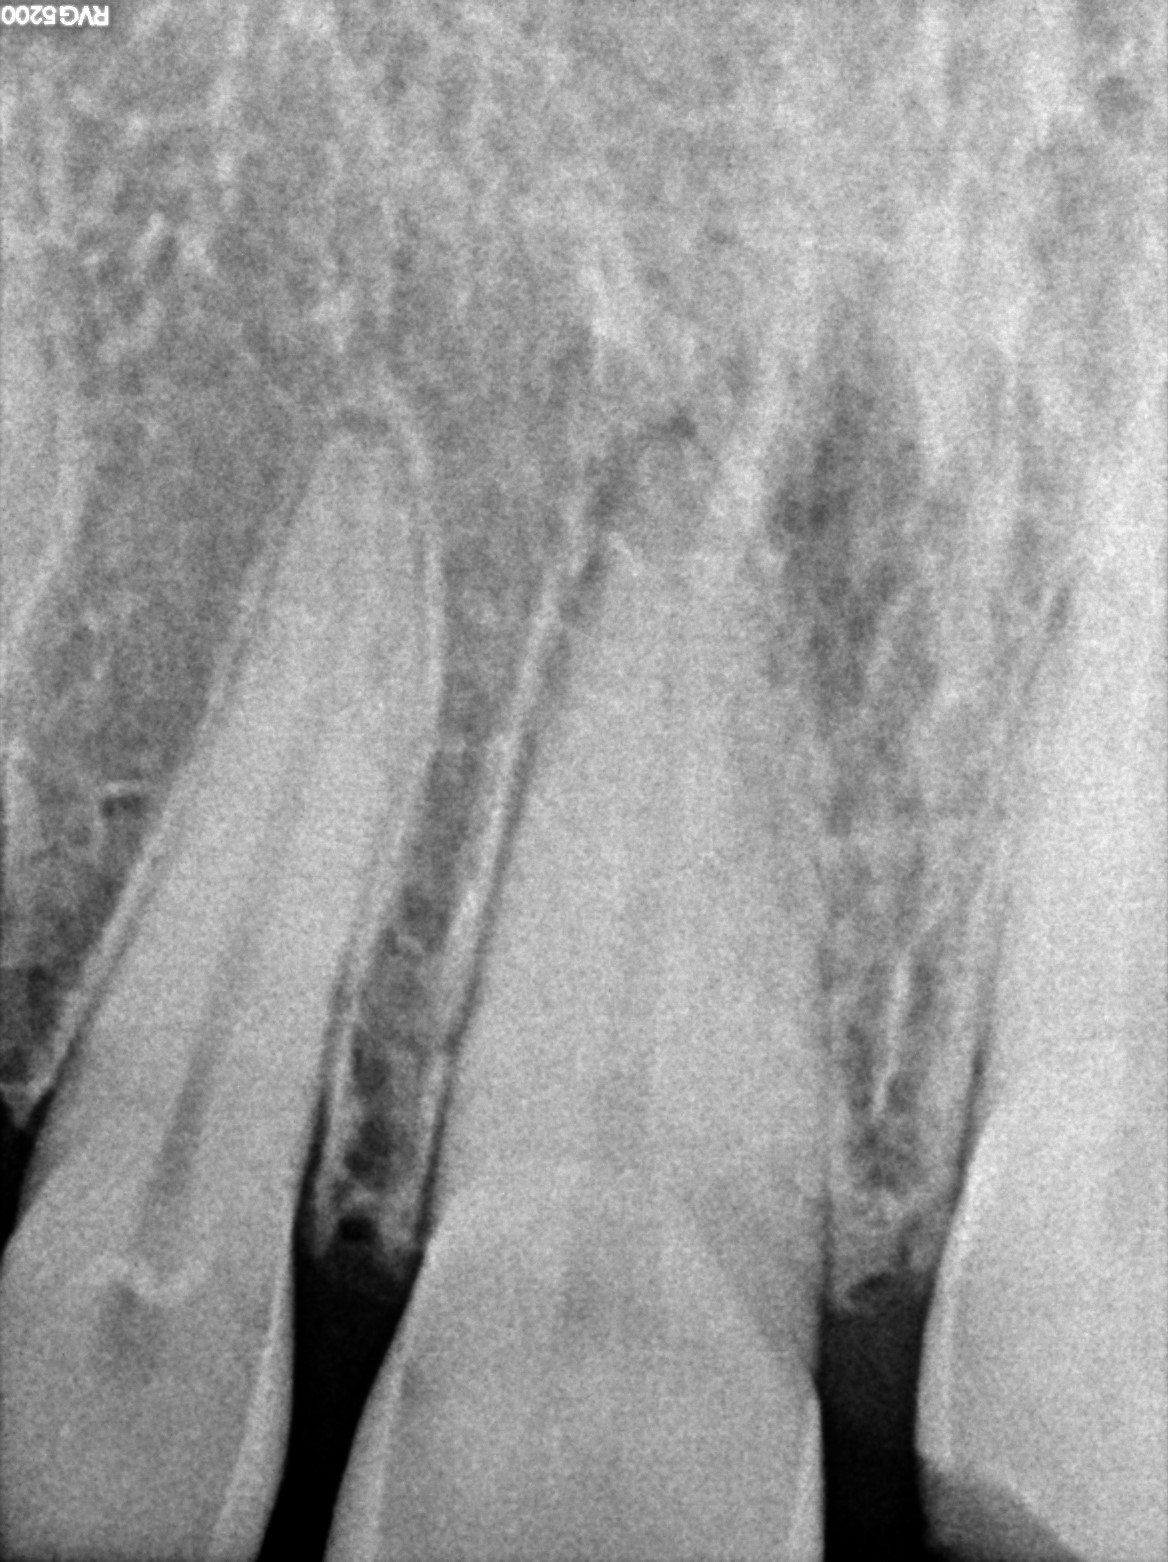

Dental Radiographs FHIR: DocumentReference · LOINC 24641-7

xray_1772727889_0.jpg

24641-7